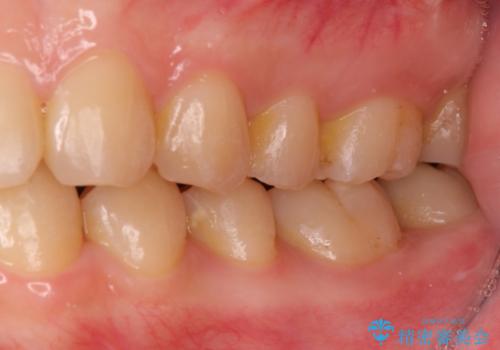

- 歯のがたつきを主訴に来院。

左右とも奥歯のがたつきがあり、左奥はすれ違っていました。

また、右奥は反対咬合になっていました。

下の前歯を一本抜歯しています。(抜歯の本数は最小限にしています。)